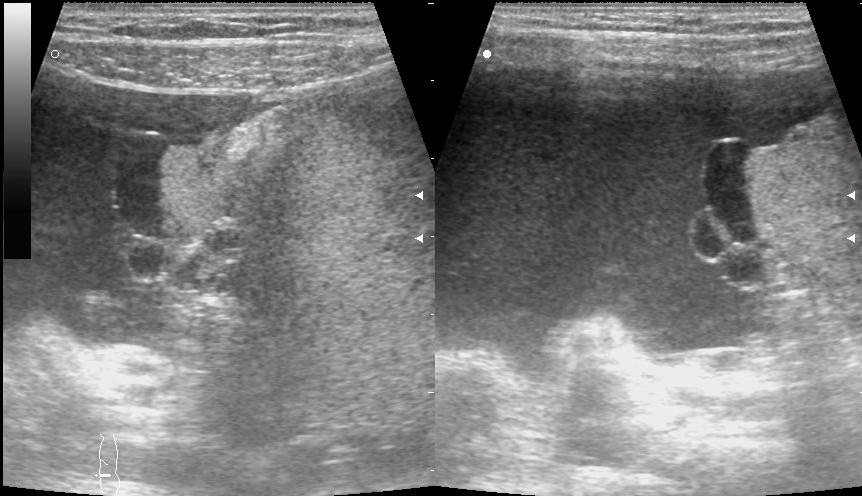

девочка 5 лет, опухоль правого яичника

опухоль правого яичника удалена 3 года назад

Если Это на стороне бывшей операции,то я за рецидив с МТ.Спасибо за бодимаркеры!

ЭТО - везде

получается и в малом тазу и в брюшной полости

выпот похож на геморальгический (???)

первый: малый таз на боку видимо рецидив местный

если то что в брюшной полости не продолжение образования из малого таза....то как вариант mts в брюшине кишечника, в большом сальнике, забр л/у